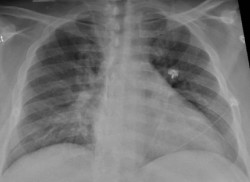

Investigadores de BRN piden "extremar la prevención" contra la neumonía adquirida en la comunidad mediante la vacunación

Los investigadores de la red Barcelona Respiratory Network (BRN) han pedido "extremar la prevención" contra la neumonía adquirida en la comunidad, especialmente entre las personas más vulnerables, a través de vacunas tales como la antigripal o la del Covid-19, que pueden conducir a esta enfermedad, así como la vacuna antineumocócica 20-valente, especialmente para mayores de 65 años, con motivo del Día Mundial de la Neumonía, que se celebra este martes.